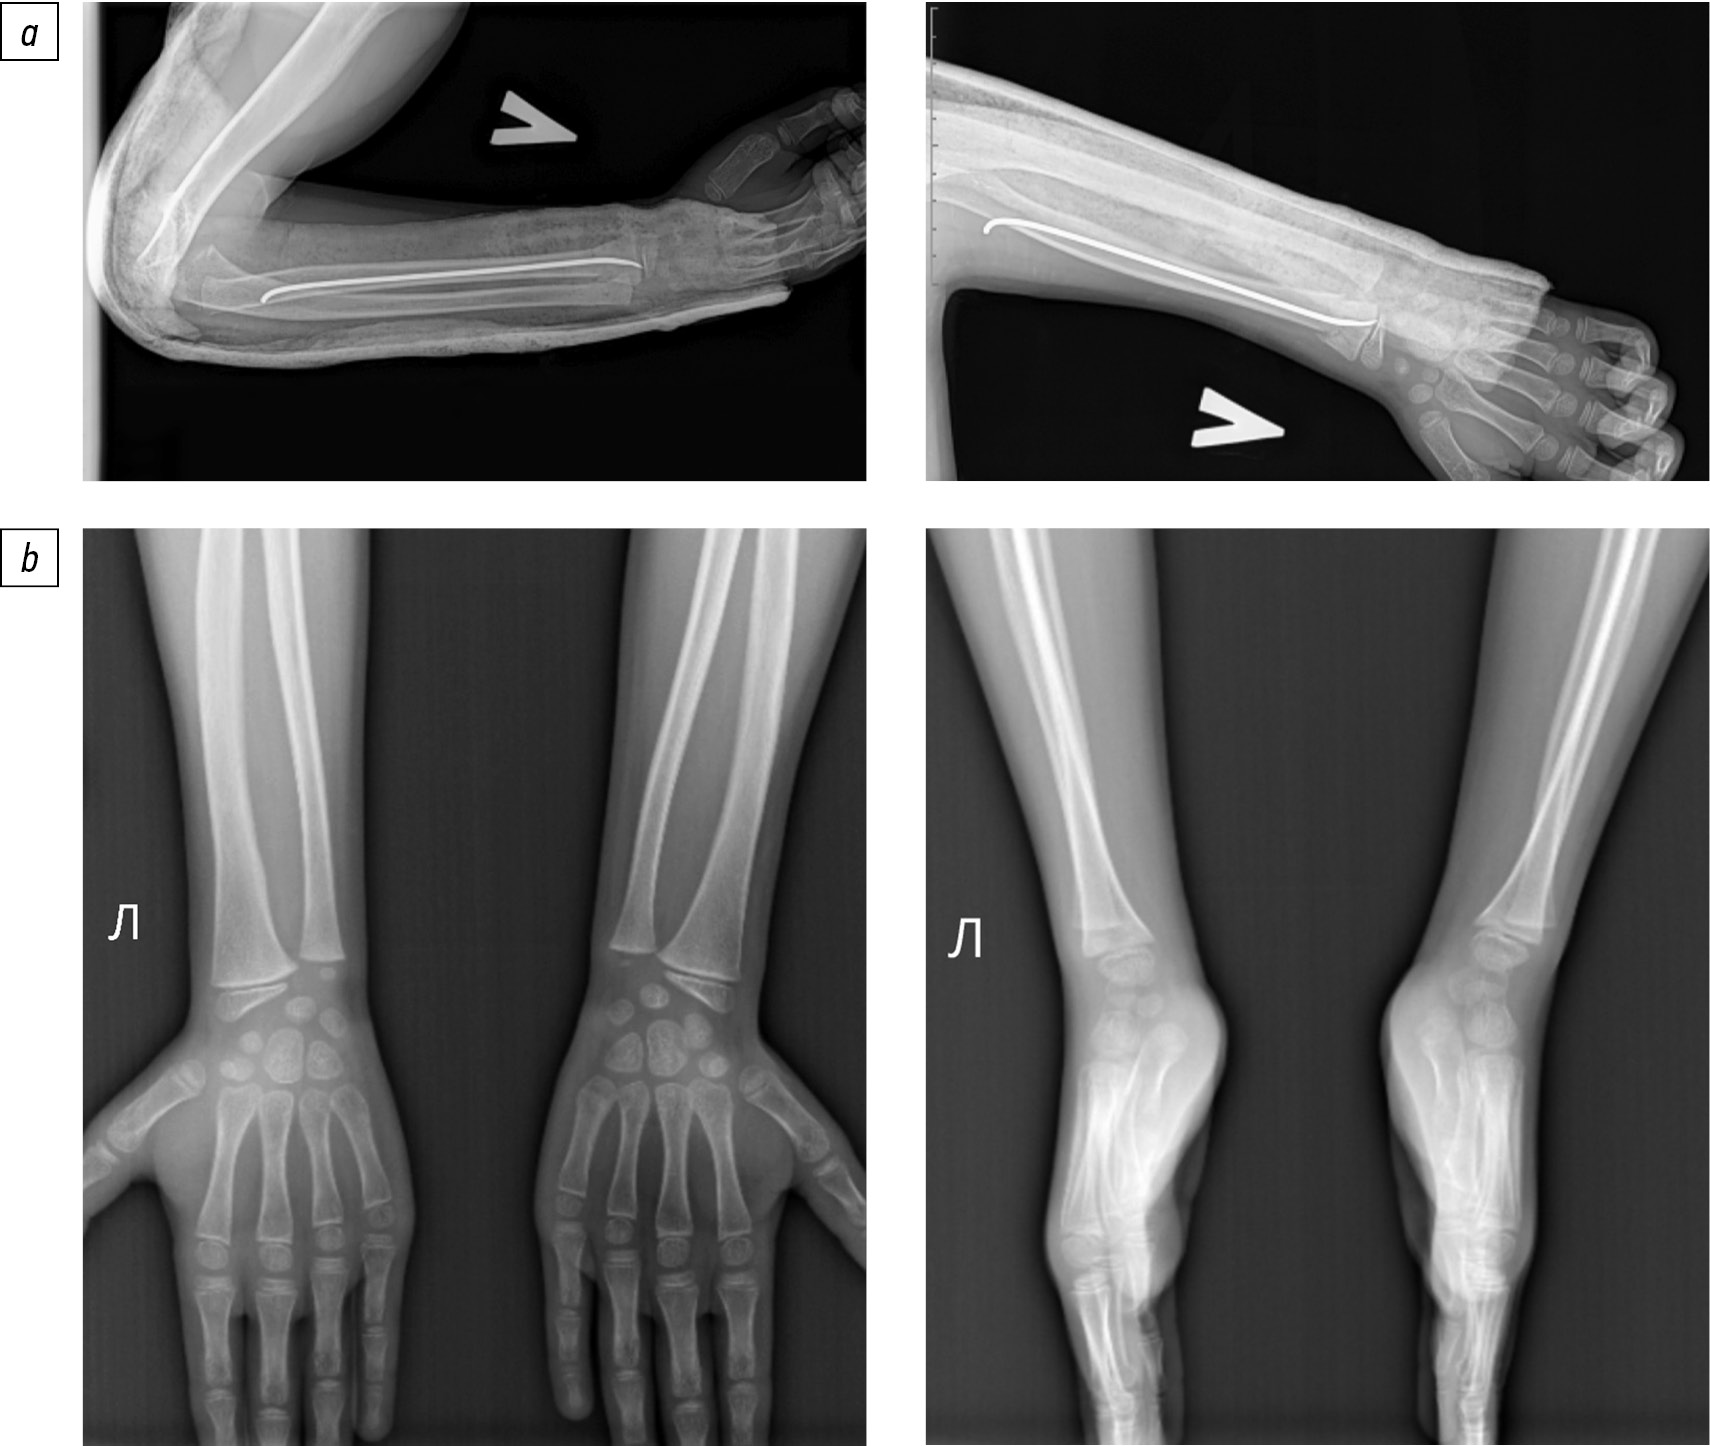

В данном исследовании среди пациентов, у которых применяли усовершенствованный способ хирургического лечения, послеоперационные осложнения были выявлены у 3 (5,77%) пациентов и не требовали повторного вмешательства. В 2 (3,85%) случаях развились постиммобилизационные контрактуры лучезапястного сустава, у 1 (1,92%) пациента отмечено локальное воспаление мягких тканей в месте введения металлоконструкции в виде отека и гиперемии, соответствующее I степени по Далю. В то же время в группе больных, пролеченных с помощью традиционного способа, у 8 (25,81%) детей возникли те или иные осложнения (р=0,01). Среди них в 3 (9,68%) случаях отмечено наличие воспалительных изменений в месте введения спиц, у 1 (3,23%) пациента развилась постиммобилизационная контрактура лучезапястного сустава. Еще у 4 (12,90%) пациентов через 4–5 нед. после оперативного лечения была выявлена миграция металлоконструкции с перфорацией кожных покровов в месте введения спицы, что потребовало проведения повторного неотложного хирургического вмешательства (удаление металлоконструкции) с увеличением сроков иммобилизации конечности, что в дальнейшем привело к развитию контрактуры лучезапястного сустава. Постиммобилизационные контрактуры у детей 1-й и 2-й групп исследования, которые не были подвержены повторному хирургическому вмешательству, были успешно купированы путем проведения курса реабилитационных мероприятий. Среди пациентов из 2-й группы, которым понадобилось повторное оперативное вмешательство, связанное с миграцией металлоконструкции, в 3 (75,0%) случаях после проведения реабилитационных мероприятий наступило улучшение, однако отмечено ограничение амплитуды движений в лучезапястном суставе при тыльном разгибании от 10 до 15° (рис. 4). У 1 ребенка (25,0%) этой категории пациентов амплитуда движений в лучезапястном суставе была полностью восстановлена. Таким образом, амплитуда движений конечности в лучезапястном суставе была восстановлена в объеме, сопоставимом с контрлатеральной конечностью, у всех 52 пациентов (100%) из 1-й группы исследования и у 29 (93,55%) детей из 2-й группы.

Рис. 4. Фото лучезапястного сустава пациента с нестабильным переломом дистального отдела лучевой кости спустя 12 мес. после оперативного лечения традиционным методом ретроградного интрамедуллярного металлостеосинтеза спицей Киршнера. Ограничение амплитуды движений в лучезапястном суставе при тыльном разгибании на 13°.